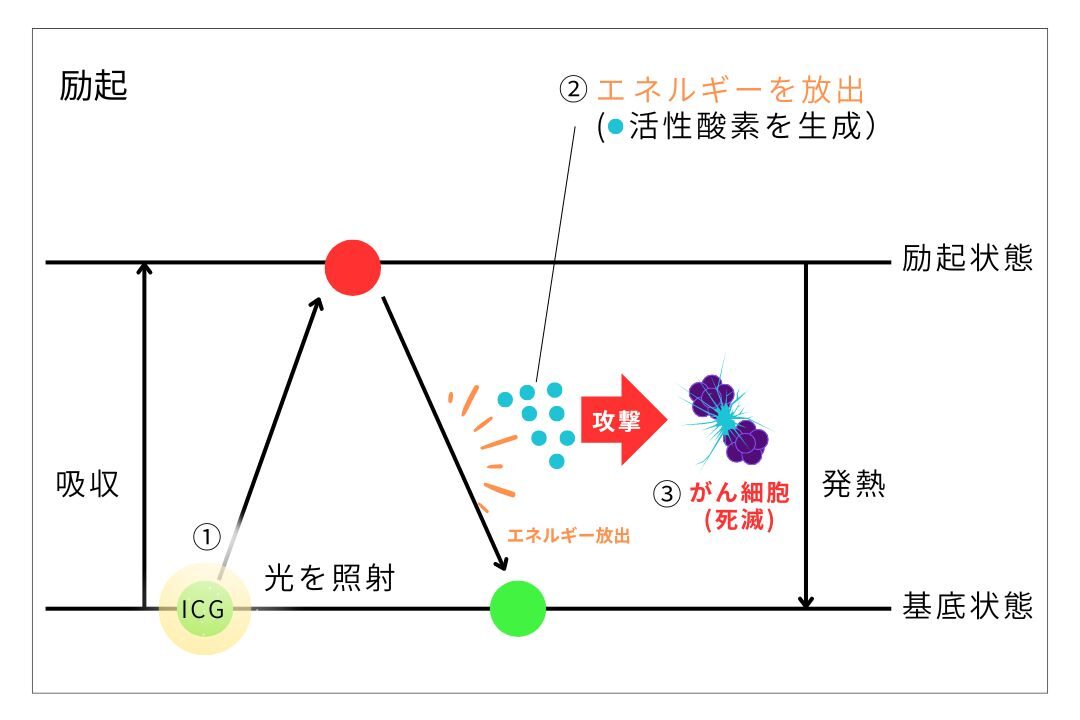

図のように薬剤はレーザー光によって活性化し、活性酸素を生成してがん細胞を破壊します。

光を光感受性物質に当てると、その物質はエネルギーを放出し、この過程で活性酸素が生成されます。

これを「光化学反応」と呼びます。がん細胞は活性酸素に弱く、この活性酸素によって破壊されます。

一方、正常な細胞は活性酸素を無毒化する「オキシダーゼ」という酵素を持っているため、破壊されません。

これも、副作用が少ない理由の一つです。